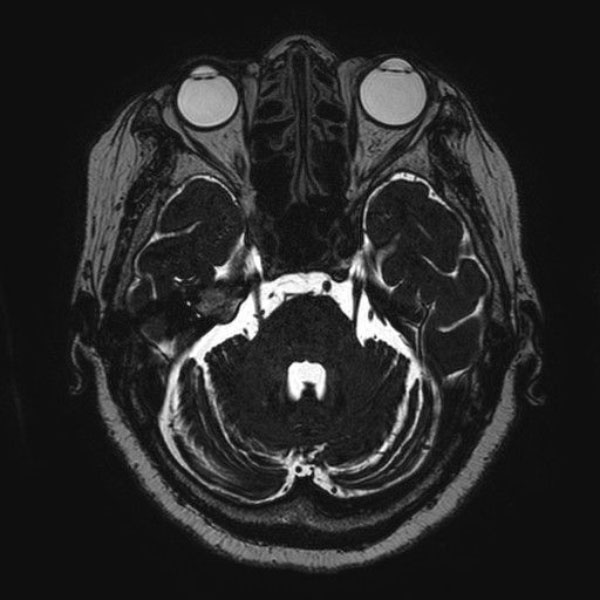

手術前

(MR1)